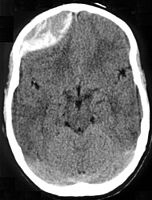

Epidural hematoma as seen on a CT scan with overlying skull fracture. Note the biconvex shaped collection of blood. There is also bruising with bleeding on the opposite side of the brain.

Diagnosis is typically by CT scan or MRI.[1] MRIs have greater sensitivity and should be used if there is a high suspicion of epidural hematoma and a negative CT scan.[3] Differential diagnoses include a transient ischemic attack, intracranial mass, or brain abscess.[3]

Epidural hematomas usually appear convex in shape because their expansion stops at the skull’s sutures, where the dura mater is tightly attached to the skull. Thus, they expand inward toward the brain rather than along the inside of the skull, as occurs in subdural hematomas. Most people also have a skull fracture.[3]

Epidural hematomas may occur in combination with subdural hematomas, or either may occur alone.[10] CT scans reveal subdural or epidural hematomas in 20% of unconscious people.[15] In the hallmark of epidural hematoma, people may regain consciousness and appear completely normal during what is called a lucid interval, only to descend suddenly and rapidly into unconsciousness later. This lucid interval, which depends on the extent of the injury, is a key to diagnosing an epidural hematoma.[3]